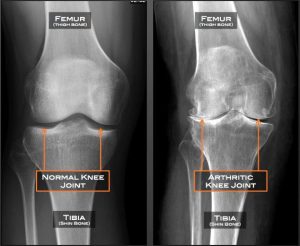

Osteoarthritis adalah jenis radang sendi yang paling umum terjadi. Bisa menimbulkan rasa sakit dan bengkak pada area persendian dan kerusakan pada tulang rawan. Jika tulang rawan alami kerusakan, maka tulang tungkai akan saling bergesekan sehingga mengakibatkan sendi lutut membengkak dan alami gangguan pergerakan.